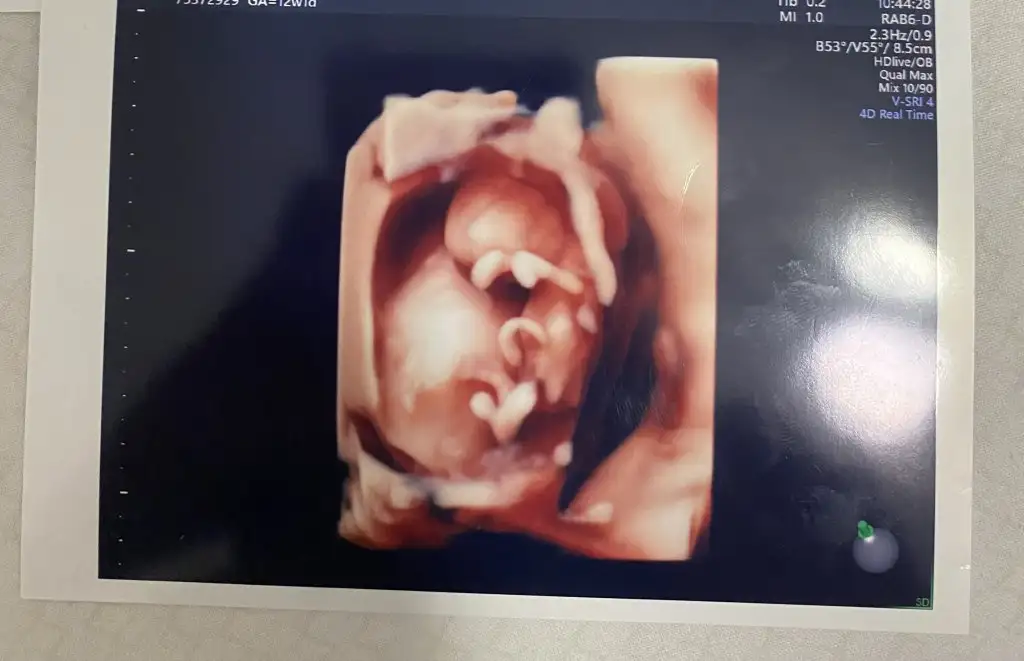

Aa baya net çıkmış hayırlı olsun12+0 da %99 erkek dedi doktorum

Evet cinsiyeti 13+3 de öğrenmiştik kız olduğunu söyledi doktorumuzBebegı hissettınız mı . Cinsıyetü belli oldumu